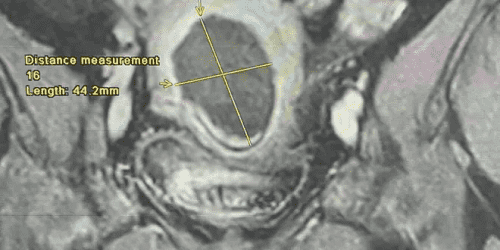

وبين أخصائي أول الأشعة التشخيصية و التصوير التلفزيوني التداخلي الرائد الطبيب محمد حمدي الحياري أن العملية أجريت تحت التخدير الواعي و تحت توجيه جهاز التصوير التلفزيوني حيث تم إدخال مسبار الكَي داخل الورم الرحمي عبرة فتحة صغيرة في جدار البطن لا يتجاوز طولها ٣مم في وقت إجمالي بلغ 30 دقيقة دون مضاعفات وغادرت المريضة المستشفى بعد 24 ساعة من الإجراء.